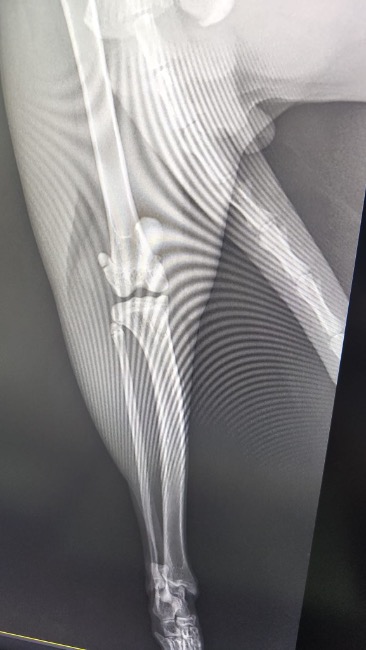

Zdiagnozowano u niego ciężką niestabilność obu rzepek, która sprawia, że każdy krok jest niepewny i bolesny. Dodatkowo lewa tylna kończyna wymaga specjalistycznego zabiegu TGR — wszczepienia protezy bloczka kości udowej.

To bardzo skomplikowana i kosztowna operacja, ale jedyna szansa, by Tymianek mógł normalnie chodzić i żyć bez cierpienia.

❗ Bez operacji jego stan będzie się tylko pogarszał!

Ból będzie narastał, pojawią się zwyrodnienia, a Tymianek — choć jeszcze taki młody — może zostać skazany na trwałe kalectwo. Już teraz widać, że ogranicza ruch, bo po prostu się boi.

🩺 Lekarze nie mają wątpliwości — czas ma tu ogromne znaczenie. Operacje stabilizacji obu rzepek oraz zabieg TGR muszą zostać wykonane możliwie szybko. Niestety ich koszt znacznie przekracza możliwości naszej fundacji. Dopóki nie zbierzemy chociaż części potrzebnej kwoty (która finalnie może okazać się wyższa), nie jesteśmy w stanie zapisać go na te zabiegi. 💔💔💔